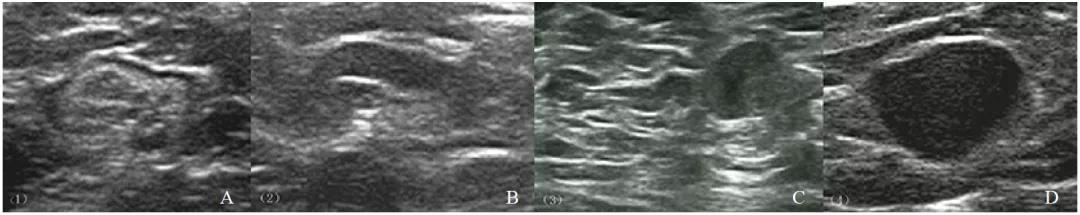

在灰阶超声声像图中,转移性及非转移性淋巴结最大皮质厚度、S、L/S的差异有统计学意义(P<0.001,表1)。S≥7.1 mm、L/S≤2.0、最大皮质厚度≥3.0 mm更多地出现在转移性淋巴结中,且最大皮质厚度是转移性淋巴结最准确的诊断标准(P<0.001,AUC=0.808)。在234例腋窝淋巴结灰阶皮质分型中,135例(57.69%)淋巴结被分为Ⅱ~Ⅳ型。转移性淋巴结所占各型比例为24.04%、38.46%、26.92%,显著高于非转移性淋巴结所占比例13.85%、16.15%、2.30%。11例转移性淋巴结被分为Ⅰ型,假阴性率(false negative rate,FNR)为10.58%。42例非转移性淋巴结被分为Ⅱ~Ⅳ型,假阳性率(false positive rate,FPR)为33.31%。灰阶皮质淋巴结分型诊断转移性淋巴结的灵敏度、特异度、PPV、NPV和AUC分别为89.4%、67.7%、68.9%、88.9和0.786(图1,表2)。

图 1 淋巴结灰阶超声Ⅰ~Ⅳ型

A:Ⅰ型,薄而均匀的低回声皮质;B:Ⅱ型,均匀的低回声皮质,最大皮质厚度为2.2 mm;C:Ⅲ型,局灶性皮质增厚,最大皮质厚度>3.0 mm;D:Ⅳ型,淋巴门结构消失。病理学检查证实A为非转移性淋巴结,B~D为转移性淋巴结。